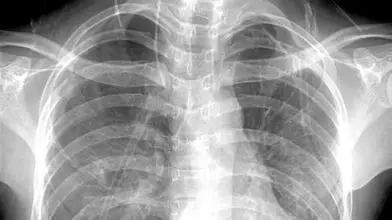

3、胸部——粗看X光片,细看CT

0.webp (5).jpg

X光胸片可粗略检查心脏、主动脉、肺、胸膜、肋骨等,可以检查有无肺纹理增多、肺部钙化点、主动脉结钙化等。

胸部CT检查显示出的结构更清晰,对胸部病变检出敏感性和显示病变的准确性均优于常规X光胸片,特别是对于早期肺癌确诊有决定性意义。但是CT检查的辐射剂量高于X光。核磁对于肺部疾病的诊断,应用非常有限。